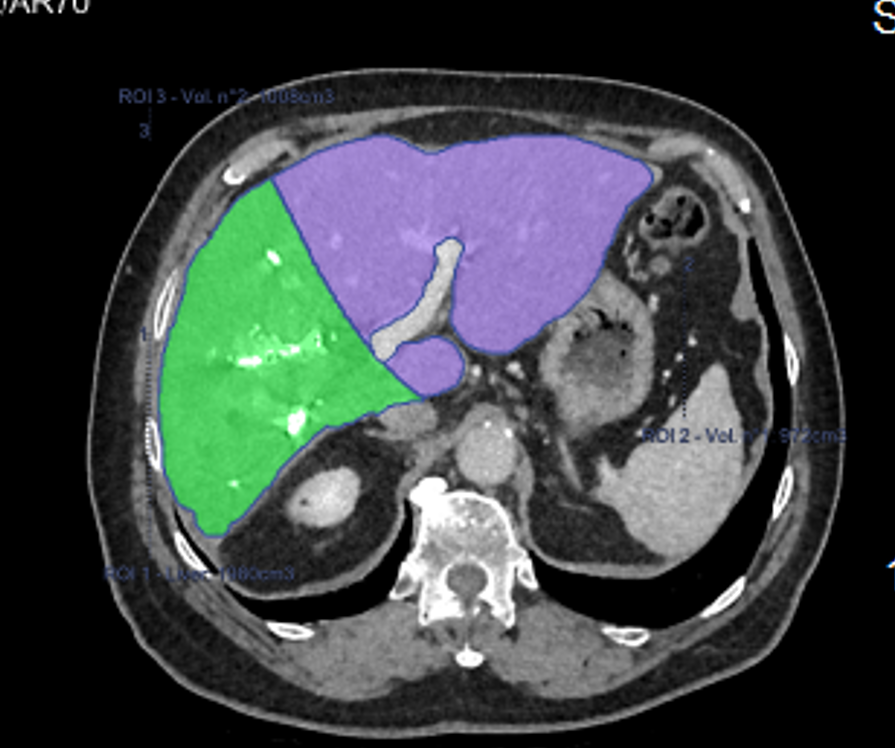

Le Scanner

- Il utilise des rayons X pour générer des images détaillées en coupes transversales de la cavité abdominale. Il peut être utilisé avec injection intra-veineuse d’un produit de contraste iodé.

- Il détecte les infections (appendicite, pyélonéphrite, abcès), les maladies inflammatoires de l’intestin (maladie de Crohn rectocolite hémorragique), les pathologies pancréatiques (pancréatite) et hépatiques (cirrhose). Il a également un rôle dans la détection et le suivi des tumeurs hépatiques, rénales, pancréatiques, ovariennes et vésicales ainsi que dans l’exploration des lymphomes.